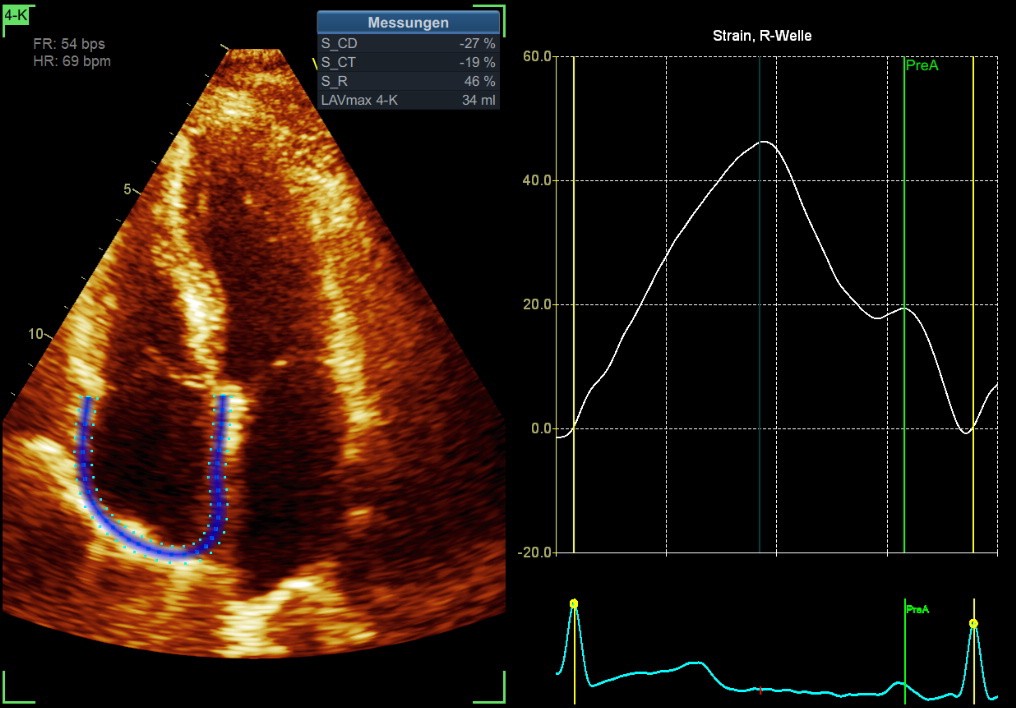

Normal values Strain Imaging — RA Strain

RA Strain is measured in the 4-ChV

A focus (optimal image) should be on the RA